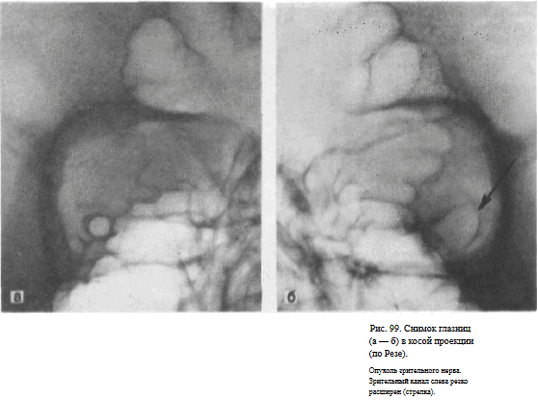

СНИМОК ГЛАЗНИЦЫ В КОСОЙ ПЕРЕДНЕЙ ПРОЕКЦИИ (СНИМОК ЗРИТЕЛЬНОГО КАНАЛА ПО РЕЗЕ)

Назначение снимка. Основное назначение снимка — получение изображения зрительного канала, Как правило, для оценки ширины и формы канала прибегают к последовательной съемке правой и левой глазницы.

Голову поворачивают в сторону и укладывают таким образом, чтобы к экспонируемой половине кассеты прилегали надбровная дуга, скуловая кость и кончик носа, а в центре ее находилась исследуемая глазница. Срединная сагиттальная плоскость головы образует с плоскостью стола угол в 40—50°, открытый кзади. Кассета размером 18Х 24 см располагается на столе в поперечном положении.

Поочередно экспонируют правую и левую половину кассеты, перекрывая неиспользуемую половину листом просвинцованной резины. На кассету накладывают неподвижную отсеивающую решетку.

Пучок излучения направляют отвесно на наружный угол глаза исследуемой стороны (рис. 97).

Информативность снимка. На снимке отображается зрительный канал, имеющий обычно неправильно-округлую форму с четкими резкими контурами. Видны также вход в глазницу, решетчатые ячейки (рис. 98, а, б). Расширение зрительного канала, возникающее при опухолях зрительного нерва, как правило, может быть достоверно выявлено только путем сравнительного анализа снимков правой и левой глазницы (рис. 99, а, б). Поэтому снимки глазниц в косой проекции по Резе всегда следует производить с обеих сторон.

Критерии правильности технических условий съемки и правильности укладки. На снимке должна быть четко видна структура костей.

Изображение зрительного канала при правильной укладке проецируется вблизи наружной стенки глазницы в виде четкой кольцевидной тени.

Наиболее частые ошибки при выполнении снимка. При неправильном угле наклона головы и неправильной центрации пучка излучения отображение зрительного канала нечеткое. При грубом нарушении правил укладки зрительный канал на снимке неразличим.